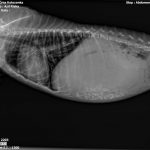

Die Röntgenaufnahmen zeigten, dass ihr Herz vergrößert ist und die Lunge bereits betroffen.

Ein Test bestätigte den Verdacht auf Herzwürmer.

Sweety ist seit sie ins Asyl gekommen ist, unter Therapie.

Die Herzwurmbehandlung ist zwar unkompliziert, aber immer sehr langwierig aufgrund der Lebenszyklen der Würmer.

Gerade bei starkem Befall muss man vorsichtig vorgehen.

Sweety atmet etwas schwer und auch ihre Leberwerte waren eine Katastrophe, erholen sich aber langsam.